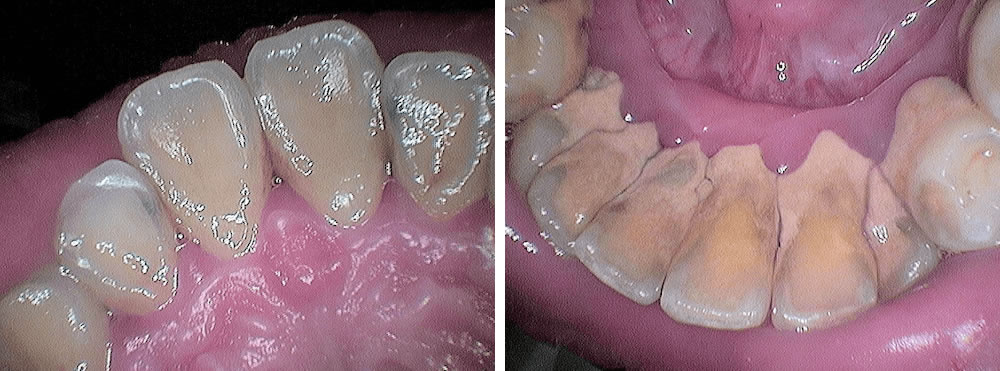

歯周病治療(歯石除去・セルフケアの指導など)の実施

セルフケアをチェック後、ブラッシング方法等を指導。その後、超音波スケーラーとハンドスケーラーで歯石を除去しました。 歯肉縁下の歯石量が多く術中は出血を伴いましたが、セルフケアで歯肉炎が改善してきたこともあり、痛みはほとんどなく施術ができています。 歯石量が多く、トリートメントは全体を6回に分けて行ないました。 ガーゼに乗せているのは、除去した歯石の一部です。